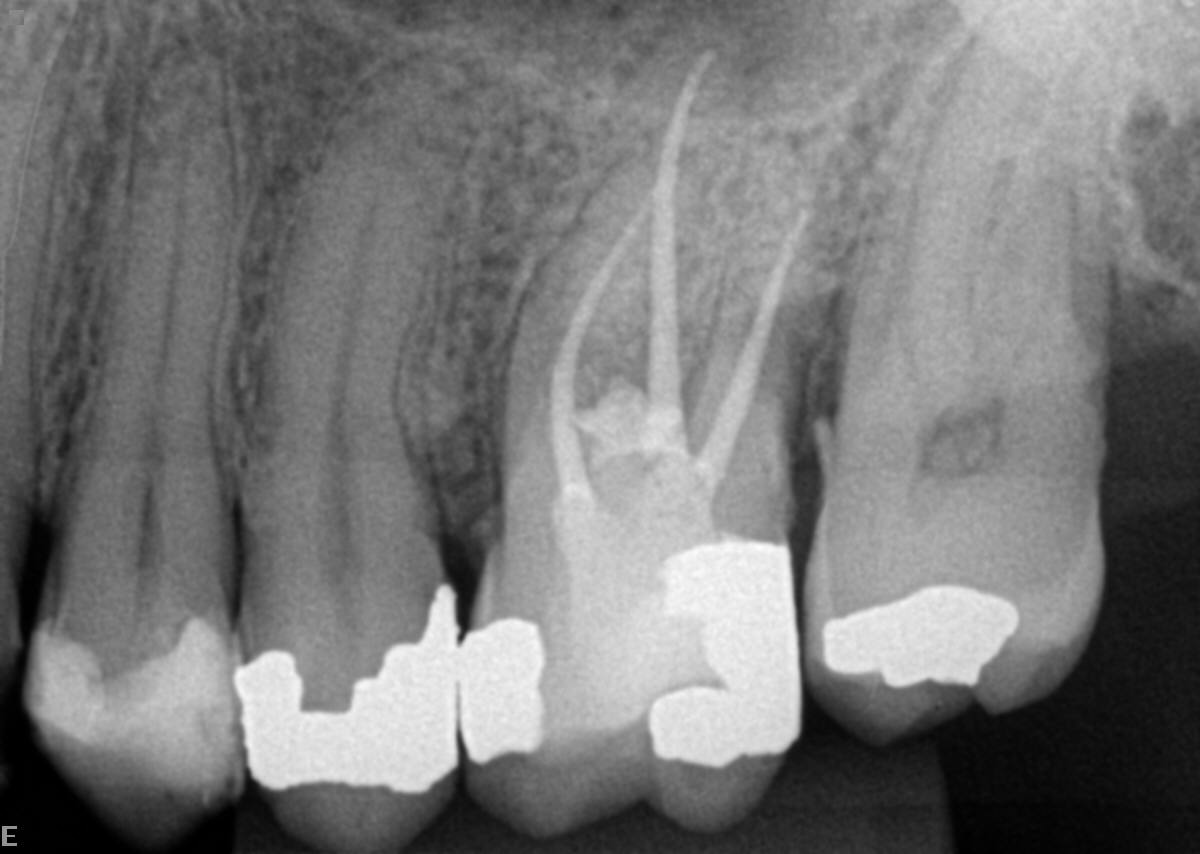

Dependendo do material biocerâmico que for levado a região da perfuração, o tempo de presa pode variar de 12 min a uma hora aproximadamente (figura 4).

A preferência é optar por materiais reparadores com presa rápida para que possamos fazer a restauração em cima desta região na mesma sessão e a obturação dos canais quando for possível (figura 5).

Por fim, o acompanhamento é muito importante e sempre deverá ser feito. O índice de previsibilidade de sucesso é bem grande em casos de fechamento de perfurações recentes. Se houver uma perfuração dentária mais antiga, esses procedimentos também podem ser feitos, porém, o ideal é medicar com hidróxido de cálcio entre sessões.